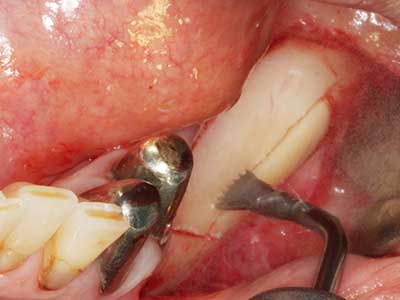

Пиезохирургията има допълнителни предимства при събиране на костни блокове. В допълнение към високата прецизност при остеотомията, описана по-горе, употребата на фините режещи накрайници значително намаляват загубата на материал. Голяма загуба на материал по време на събиране може да се очаква с дебелите накрайници, особено при употреба на борери Линдеман (Lakshmiganthan, Gokulanathan et al. 2012). Базалното разделяне, което е необходимо, особено за присадка на блок при ретромолар, е улеснено от специално създадени правоъгълни триони. В резултат на това, пиезохирургията е разглеждана като прецизна, улеснена и безопасна процедура за събиране на костни блокове в ретромоларното пространство (Happe 2007) (Фиг. 1-12).